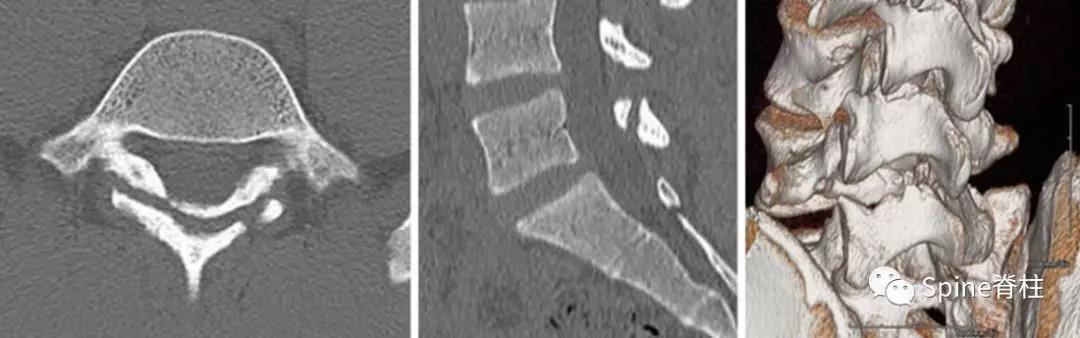

图:L5半椎板裂

17岁芭蕾舞者,腰痛7个月

CT示:左侧为椎板裂(箭头),右侧为峡部裂(箭头)